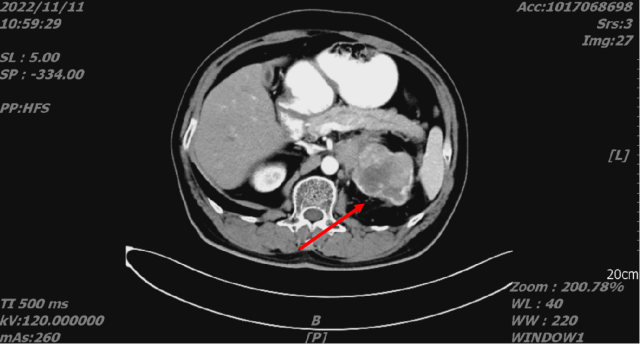

舒尼替尼治疗后,2022-11-11 复查 CT

1. 结合临床,左肾癌治疗后,较前片 2022-08-15 略饱满;左侧肾上腺受累;考虑肝转移,较前进展。

2. 双肺转移,较前变化不著

3. L5 双侧椎弓崩解;L2 椎体致密灶,变化不著。

Treatment 腹腔镜减瘤性肾切除术